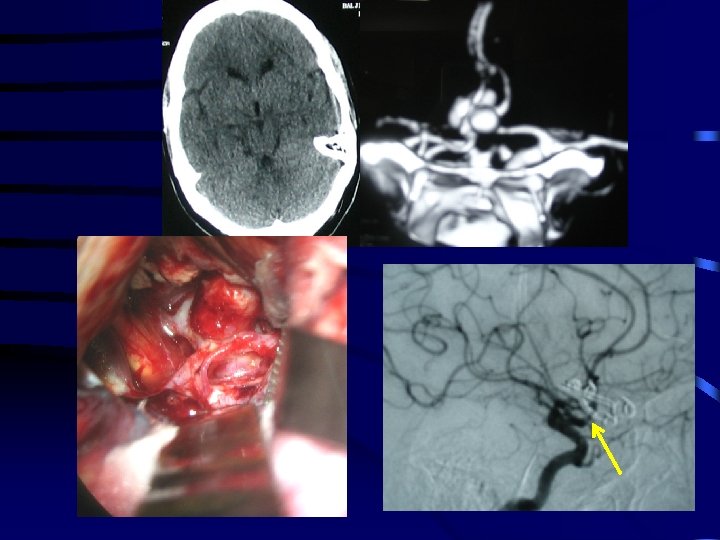

Paediatric SAH Pre -op Post-op

PRE - OP Moya disease POST- OP